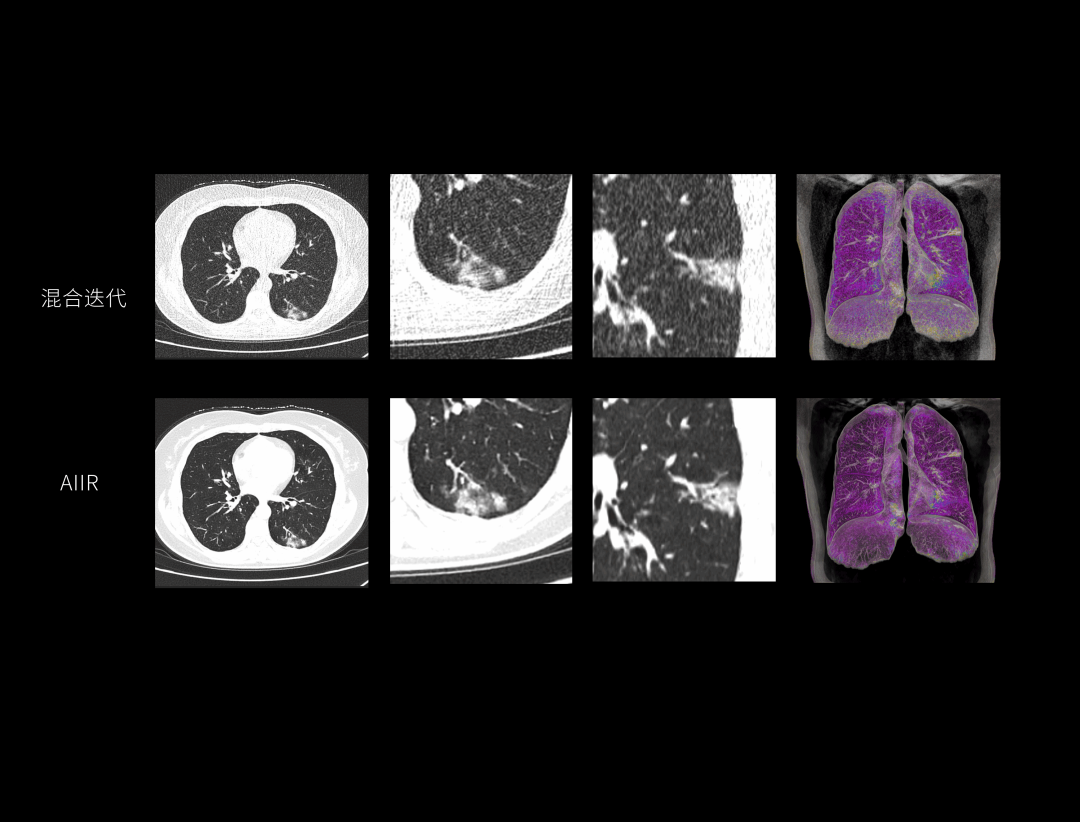

AIIR双精度图像感知

AIIR图像重建提升结果图像可解释性与算法鲁棒性,获得低剂量下的高清成像,超越传统,引领CT成像新标准